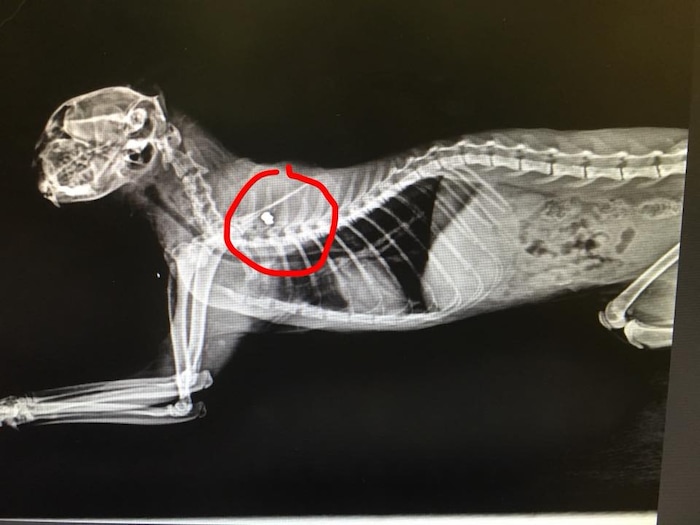

The second victim was a cat named Lucky who had been shot near the end of May. After being treated by a vet, it was determined the black cat had a bullet lodged near his spine. According to Linda Thomas, the medical director of RSQ, Lucky couldn’t move or even lift his head.

“Every day, he gets better,” Thomas said. “The bullet went into his neck and is lodged in his shoulder, really close to his spinal column. They don’t want to remove the bullet.”